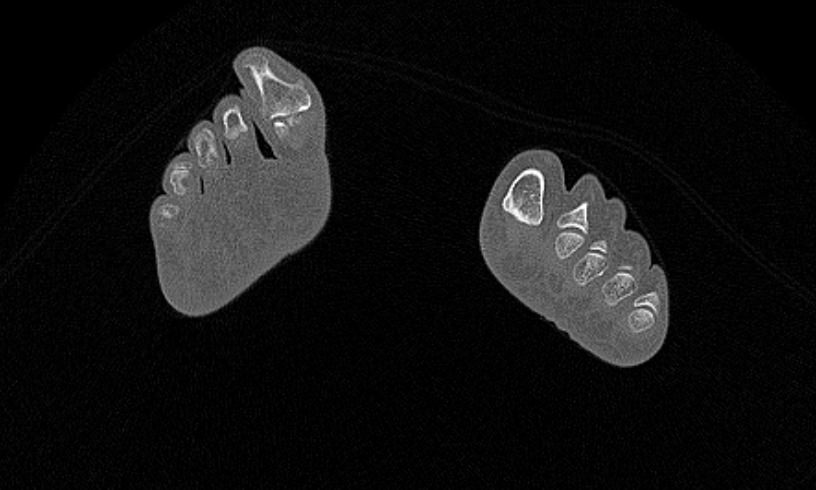

Наиболее точным и информативным методом обследования костных структур стопы является мультиспиральная компьютерная томография. КТ относится к лучевым методам исследования, то есть для визуализации внутренних органов применяется сканирование при помощи рентгеновского излучения, а затем полученные данные проходят цифровую обработку. В результате получается объемная реконструкция исследуемой области, которую можно увеличить, повернуть в разные стороны, оценить расположение анатомических структур и измененных участков в пространстве.

В наших диагностических центрах обследование стопы выполняется на современных мультиспиральных компьютерных томографах последнего поколения TOSHIBA AQUILION. С помощью аппаратов проводится скоростное мультисрезовое сканирование, во время которого одновременно производится большое количество снимков высокого разрешения. При этом уменьшена доза рентгеновского облучения для пациента.

С помощью мультиспиральной КТ проводится точная диагностика травм стопы, позволяющая оценить расположение костных отломков. Метод КТ применяется для визуализации костей стопы при планировании хирургического вмешательства, затем в послеоперационном периоде для оценки правильности репозиции костных отломков и для контроля процессов регенерации кости.

Метод КТ наибольшую информацию дает о состоянии костных структур, так как кости в большей степени поглощают рентгеновские лучи и поэтому хорошо видны на снимках. Для повышения диагностических возможностей метода, в частности, для улучшения визуализации мягких тканей, мышц и связочного аппарата дополнительно используется контрастное усиление.